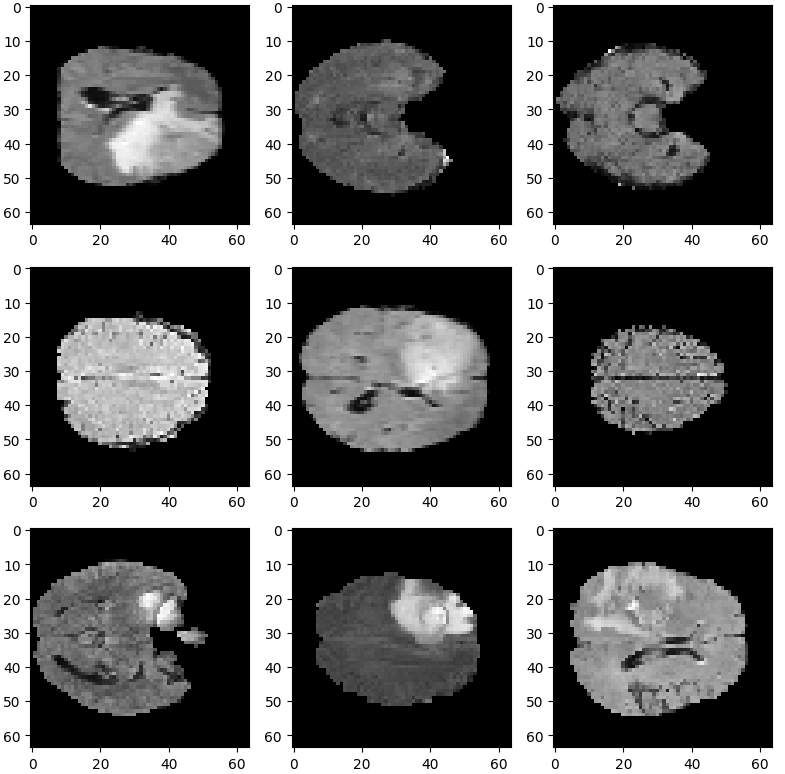

DecathlonDataset

医学分割十项全能挑战数据集(DecathlonDataset)是一个用于医学图像分割任务的数据集(very hot!)。该数据集包含来自不同医学影像模态(如MRI、CT等)的图像数据以及标签。数据可以从官网进行下载

MONAI的DecathlonDataset会自动该数据集,并且分好了训练、验证和测试集。它还基于monai.data.CacheDataset类来加速训练过程。

task="Task01_BrainTumour",